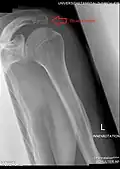

Radiograph of the shoulder showing an os acromiale

Os acromiale

The acromion has four ossification centers called (from tip to base) pre-acromion, meso-acromion, meta-acromion, and basi-acromion. In most cases, the first three fuse at 15–18 years, whereas the base part fuses to the scapular spine at 12 years. However, in between 1% and 15% of cases, this osseous union fails and the acromion remains separate as an accessory bone. This condition is referred to as os acromiale, but rarely causes pain. Earlier estimates of its prevalence were as low as 1.4%, and this higher estimate was made by Sammarco in the year 2000, based on radiographic and anatomical studies.[6][7]

Four types of os acromiale can be distinguished:[8]

- A non-union between the meso- and meta-acromia, the most common or typical os acromiale

- A non-union between the pre- and meso-acromia

- A non-union between the pre- and meso-acromia; and between the meso- and meta-acromia, atypical

- A non-union between the pre- and meso-acromia; between the pre- and meso-acromia; and between the meta- and basi-acromia

Although historically regarded as an incidental finding, the os acromiale may occasionally produce symptoms from subacromial impingement or instability at the site of non-union.[9] In people with symptoms of os acromiale, dynamic ultrasound sometimes shows hypermobility in the area during shoulder movement, or graded compression with the probe.[10]